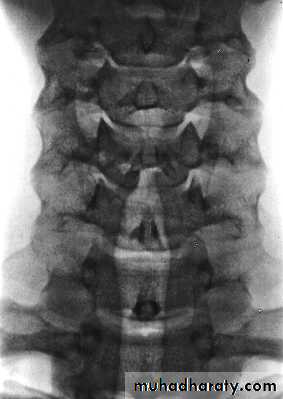

Cervical Spine X-RayLateral radiograph

A/P radiographThoracic Anatomy